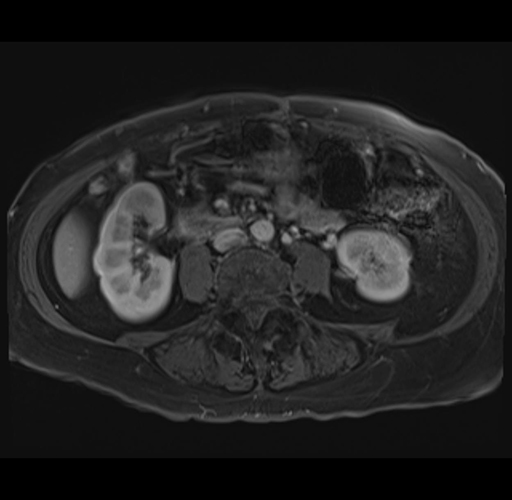

Axial Venous